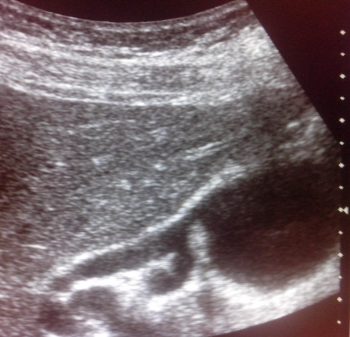

киста холедоха